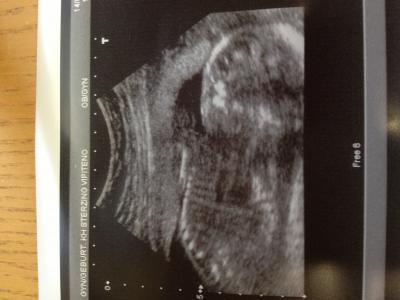

Hey Mädels, bin total erleichtert, was der DA erkennen konnte war alles in Ordnung, den 4- Kammerblick, Magen, Blase, sogar die Rippen hat man schön gesehen, lag mit dem Rücken zu uns desshalb ist das Foto nicht besonders schön geworden, aber egal...!! Biparietaler durchmesser ist 50,3 und Femurlänge 33,6, also total Zeitgerecht entwickelt! Länge konnte er leider nicht ermittel ...! Muss morgen zur Blutentnahme, da ihn der TSH Wert zu niedrig vorkommt u er nicht versteht wieso ich die Tabletten immer weiter nehmen musste...! Ach ja u es wird sehr wahrscheindlich ein Mädchen, juhuuuu :-)))!!!! Lg

Bild zu Fa Bericht - Forum für Mai - Mamis